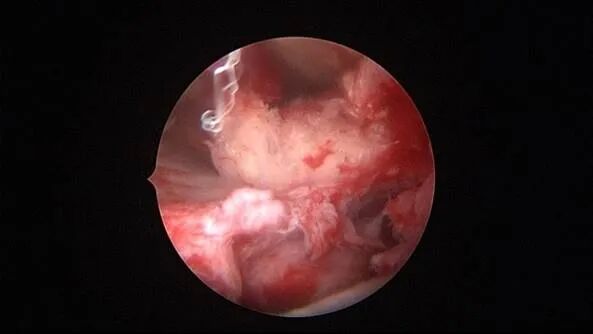

外院取环失败,子宫从切口憩室处穿孔

宫腔操作假道发生率较高,穿孔发生率较低,假道和穿孔原因一致,力度大了就穿孔了。假道或穿孔大多发生在门诊取环、人流、清宫等病例,尤其是绝经后取环占比最多。子宫位置特殊、宫颈管狭窄,探针探查、扩宫或取环钩操作时形成假道或穿孔,立即停止操作,经评估后做宫腔镜处理。宫腔操作动作要轻柔,注意子宫收缩节律,不要在子宫收缩时突然进入宫腔。穿孔可能损伤宫底或宫腔前后壁血管,缓慢持续出血导致盆腔积血。穿孔后是否探查盆腔、修补子宫需详细评估病情:血常规、B超、腹部刺激症状、失血体征、后穹隆穿刺等,大多数穿孔不需要手术探查。宫腔镜术中出现难以控制的出血大多发生于靠近子宫动静脉的粘膜下肌瘤、侧壁宫腔粘连、胚物残留合并动静脉瘘及子宫纵膈手术等,直视下电凝止血是最佳办法,球囊压迫止血影响因素太多,包括出血部位、动静脉区别、血管大小、子宫收缩情况、球囊大小、牵拉球囊力度等,效果一言难尽,尽量不采用。腹腔镜下缝合子宫壁、经阴道宫颈侧壁缝合(都不一定能缝到出血血管)、艾丽斯钳钳夹宫颈等方法可压迫止血或明显减少出血。手术越熟练、缩短手术时间、快速完成手术,手术越安全,避免严重水中毒发生。甘露醇或5%葡萄糖膨宫,手术每隔20~30分钟,建议速尿(半衰期为30~60分钟)半支静推;生理盐水膨宫,手术时间持续30~45分钟,速尿半支静推,总时间最好控制在60分钟以内,不要超过90分钟,必要时分次手术。速尿具体使用量及间隔时间根据膨宫介质、膨宫压力、手术难易及时间长短、创面及血管暴露情况、病人生命体征、麻醉情况等决定。

为了宫腔镜手术平稳顺利进行,宫腔镜术前准备及安全评估非常重要,尤其是充分的安全评估能有效减少并发症的发生。阴道情况:萎缩、纵膈、斜膈等可能导致扩阴器置入困难。肥胖病人、高个子病人阴道很深,宫颈可能难以暴露;宫颈情况:绝经后病人宫颈萎缩、狭窄、坚硬,加之穹隆展平,宫颈难以夹持、难以扩张;宫颈管弯曲、宫颈肌瘤、巨大息肉、粘膜皱襞隐窝、巨大纳囊等,可能阻挡宫腔镜进入宫腔;子宫情况:子宫萎缩,宫腔狭小,子宫极度前屈、后屈、侧屈等极端位置常常导致宫腔镜置入困难;既往盆腔手术史:子宫与盆腔器官粘连可能导致子宫极端位置,或者宫深超出预期。近期手术情况:外院取环失败、人流不全、宫腔探查或试图分粘中途放弃等病人,子宫可能存在假道、穿孔或盆腔积血等损伤。这类病人评估重点:前次手术医院级别、既往分娩情况、安环多少年、月经情况、闭经或绝经时间、手术日期、手术时间长短、是否麻醉、术后有无腹痛、有无阴道出血、B超情况、腹部平片、血糖血压等。宫腔镜术前需再次复查B超,手术医生到B超室了解子宫位置、大小、有无损伤、节育环种类及位置、是否嵌顿、盆腔有无积液等细节。